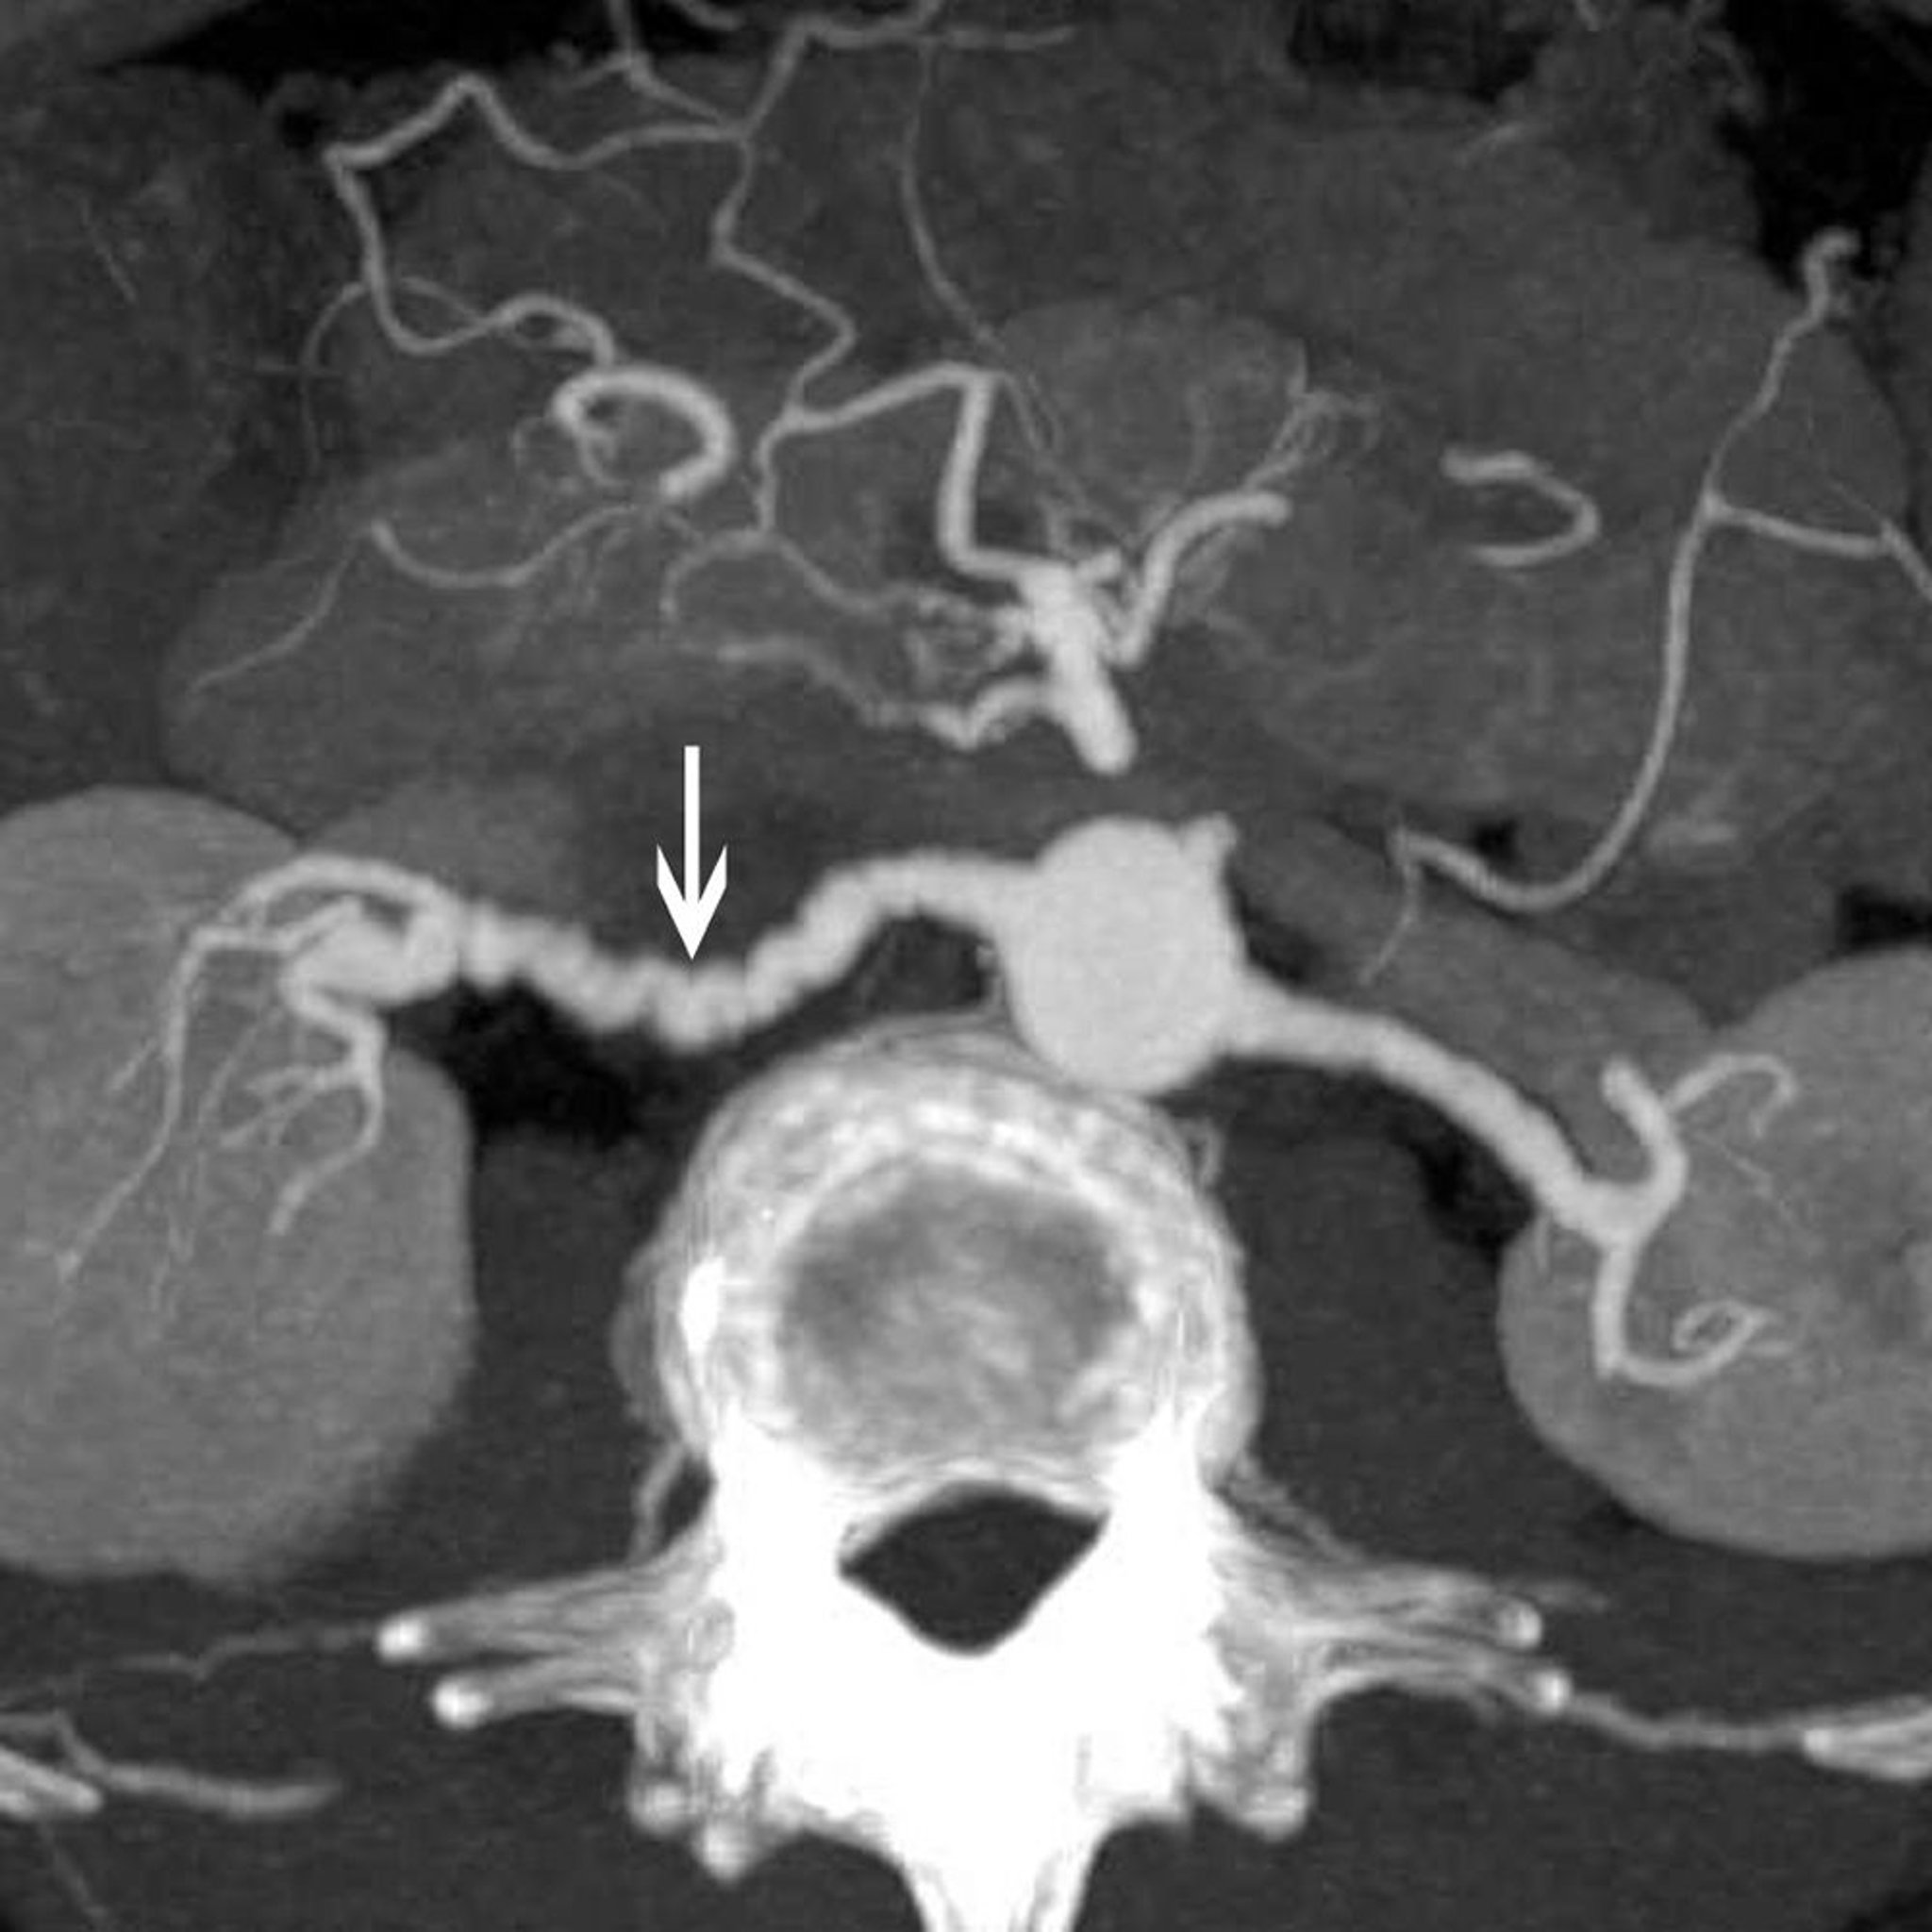

Cette image montre le classique signe du "collier de perles" (flèche) chez un patient atteint de dysplasie fibromusculaire de l'artère rénale.